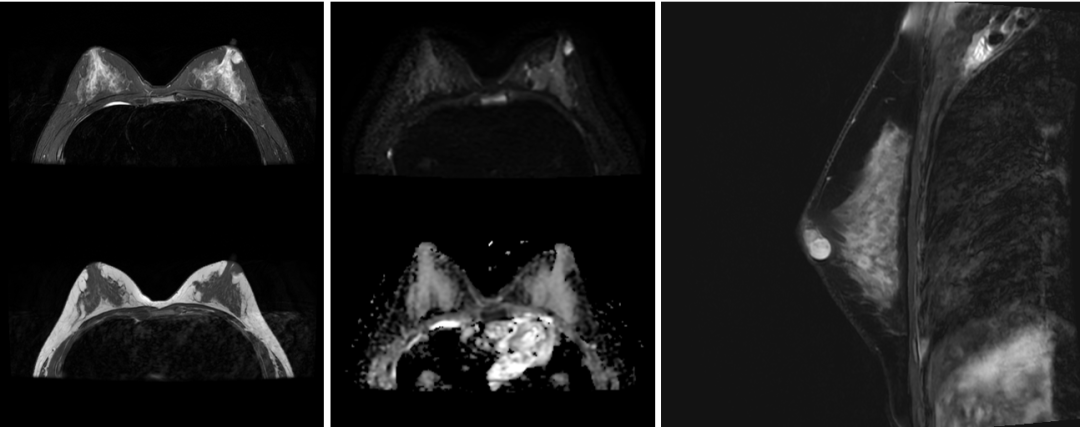

乳腺:乳腺癌筛查、假体评估、保乳术后随访等。

乳腺